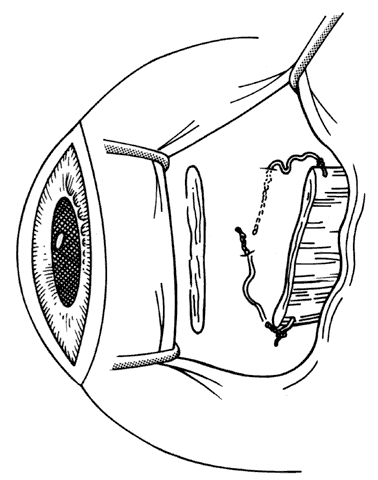

Fig. 16. Wescott scissors and toothed forceps are used to reflect conjunctiva (top) for removal of subconjunctival fibrous tissue (bottom).

Fig. 17. When there is extensive fibrous proliferation between the conjunctiva and the muscle, Wescott scissors are used to cut it free from both surfaces. An attempt is made to remove this tissue without disturbing the muscle capsule or cutting into the insertion of the rectus muscle.

Fig. 18. This fibrous tissue was removed from a patient with prior strabismus surgery. Note the connective tissue component. Thick bands of compact collagenous scar tissue infiltrate orbital fat (hematoxylin and eosin, X 100). (Courtesy of Bruce L. Johnson, MD)